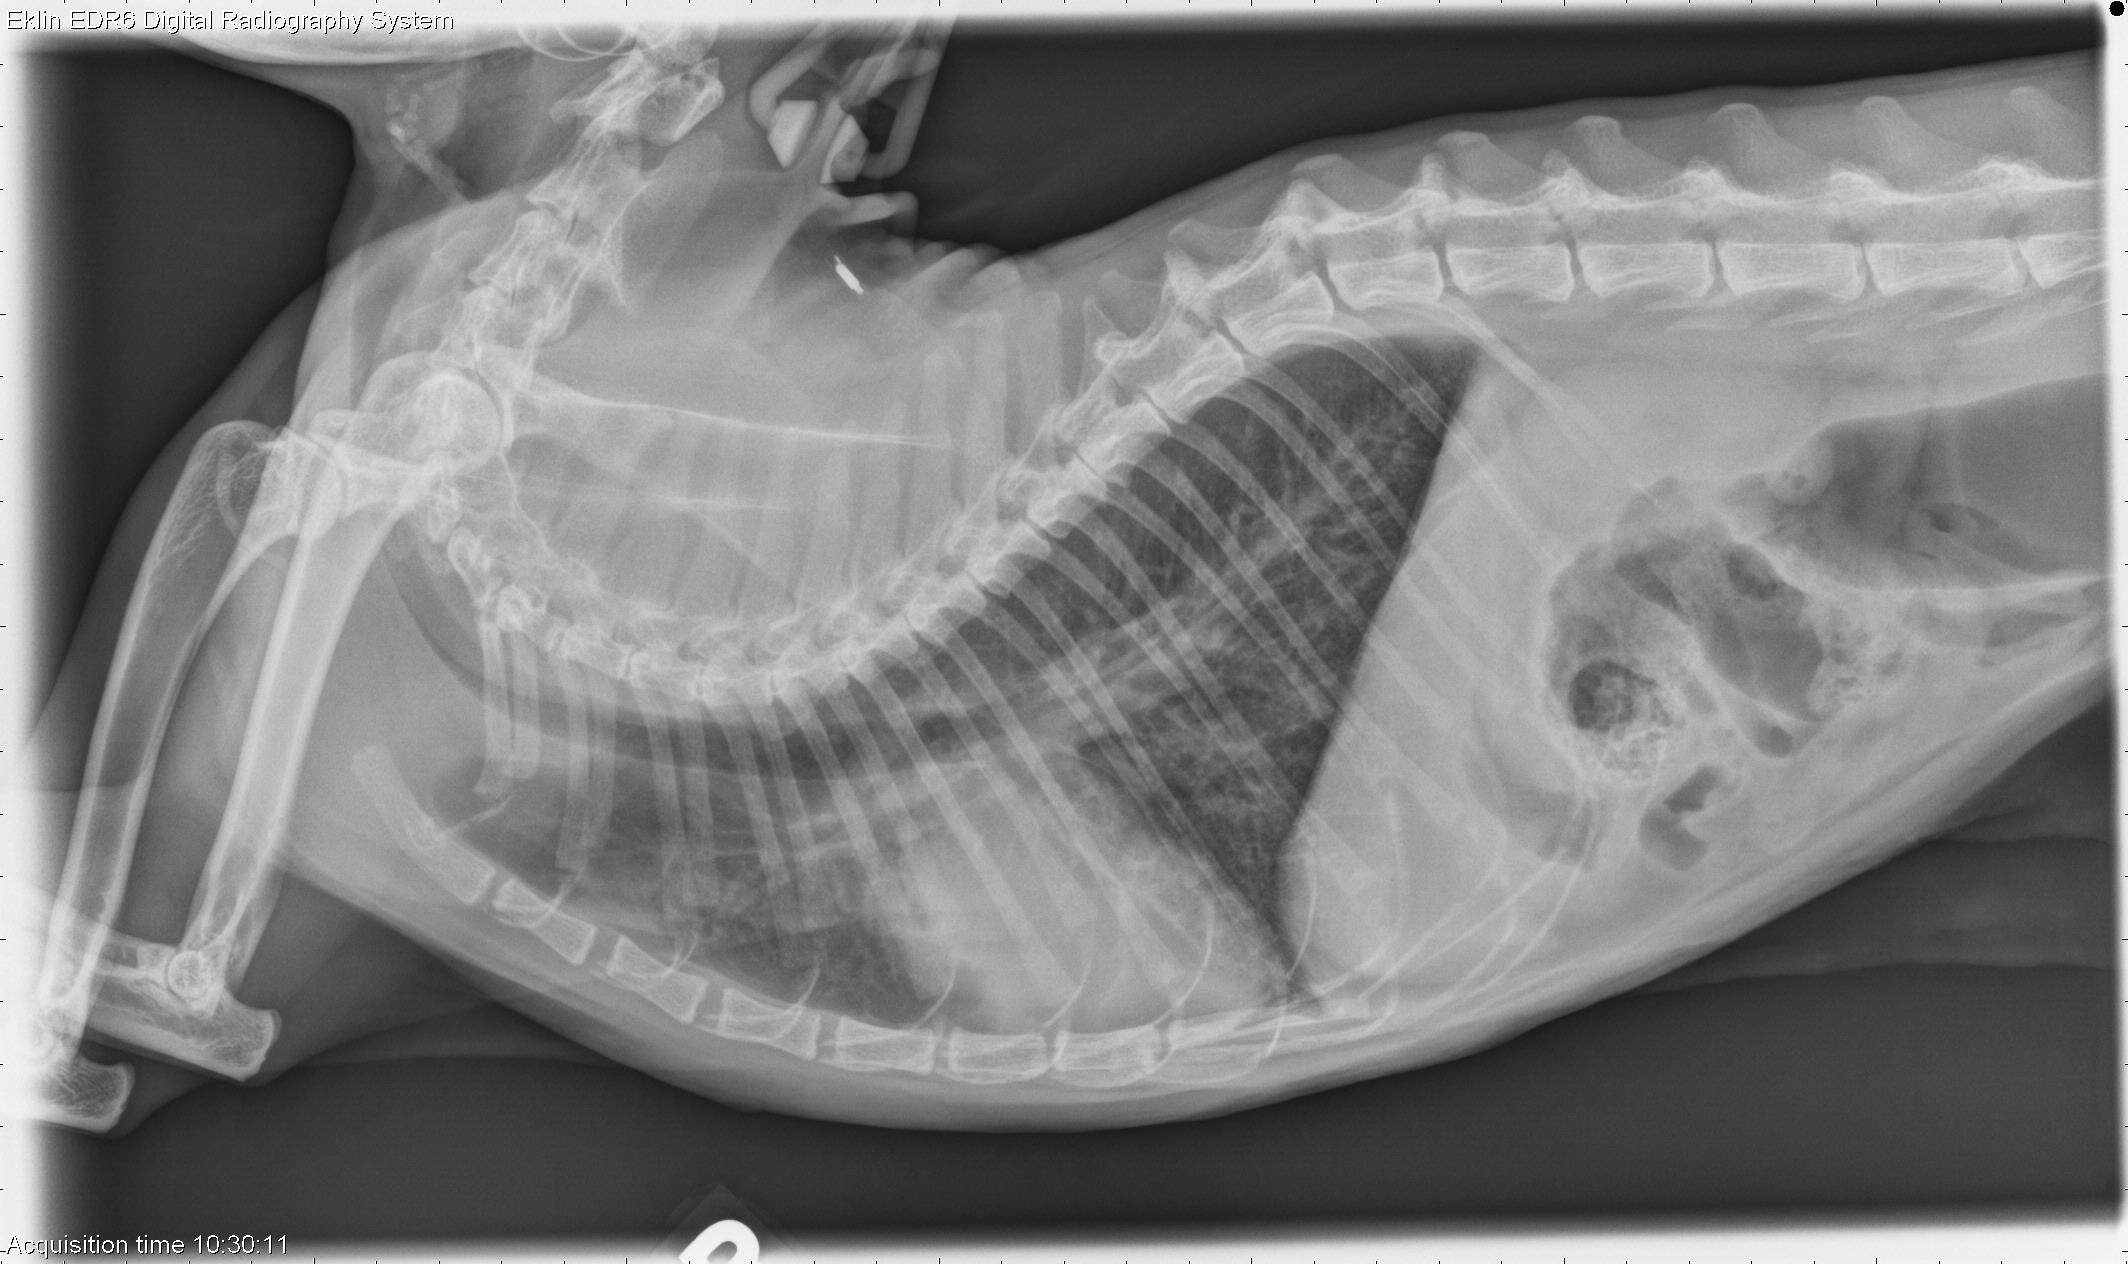

Lung pulmonary edema radiograph lateral in Cats (Felis) Vetlexicon Pulmonary Edema Cat X Ray Thoracic radiography is one of the most commonly employed diagnostic tools for the clinical evaluation of cats with suspected heart. Pulmonary edema, the abnormal accumulation of fluid in the tissue, airways, or air sacs (alveoli) of the lungs, may occur along with circulatory. There is a general progression of signs on a plain radiograph that occurs as the pulmonary capillary. Pulmonary Edema Cat X Ray.

Lateral thoracic radiograph image of a cat with pleural effusion due to Pulmonary Edema Cat X Ray To describe the radiographic appearance of pulmonary oedema in cats with cardiac failure. Pulmonary edema, the abnormal accumulation of fluid in the tissue, airways, or air sacs (alveoli) of the lungs, may occur along with circulatory. Thoracic radiography is one of the most commonly employed diagnostic tools for the clinical evaluation of cats with suspected heart. There is a general. Pulmonary Edema Cat X Ray.